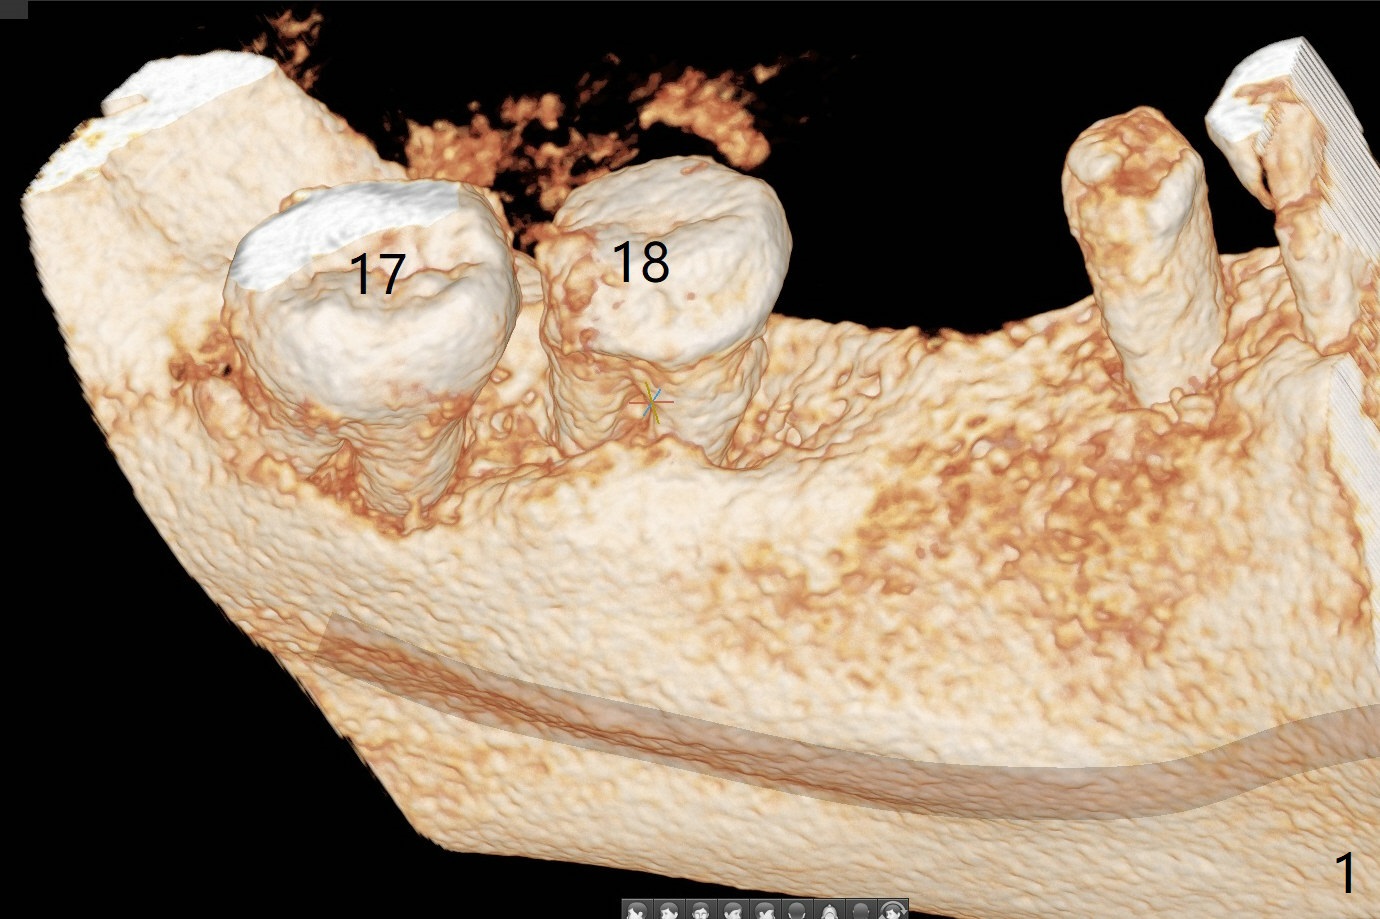

Re-analysis of preop CT reveals extensive bone loss around #18 (Fig.1 (lingual view)). Blood is withdrawn for sticky bone. After implant placement (Fig.2), sticky bone is placed at #18 (Fig.3 red dashed line (yellow: superior border of the Inferior Alveolar Canal)). PRF membrane and an immediate provisional FPD (#18-20) further keep the bone graft in place for healing. Four months postop, the patient reports difficulty in mastication on the left and requests extraction of the tooth #20 for implant (Fig.4). The implant will be placed lingually, while socket shield will be performed buccally (Fig.5 S) to keep bone graft in place. The implant at #19 is equicrestal (Fig.6); the one at #18 is apparently supracrestal buccally (Fig.7). Since there is a lot of scattering from nearby crowns, the implant at #20 will be placed free hand. To overcome the thick dense lingual plate (Fig.8 L), osteotomy is initiated (Fig.9 red line) in the middle of the lingual wall of the extraction socket (black area) on the top of the socket shield (S). After the last drill (3.5x11.5 mm, Fig.10 pink) and before 4x11.5 mm implant, use Lindamann bur to remove the coronal portion of the lingual plate (Fig.11 red line) to prevent implant buccal deviation.